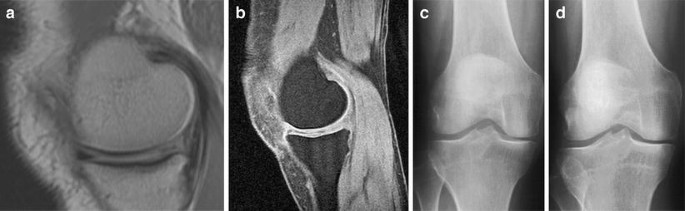

In the KL < 2 group, a definite association occurred between meniscal subluxation and radiographic progression of JSN 2 years later (crude RR 7.85; crude CI 1.56–24.86; adjusted RR 11.3; adjusted CI 2.49–29.49). An example is shown in Fig. 1a–d. A trend was seen for BML and cartilage loss, but no other association was shown between the progression of JSN and any other MR parameter (Table 2).

Coronal PD dual SE images medial meniscus subluxation (a) with a sagittal 3D T1-weighted spoiled gradient echo frequency-selective fat-suppressed image of normal hyaline cartilage (b) with X-rays of subsequent joint space narrowing in the medial compartment after 2 years (d) compared to baseline (c) in the KL < 2 group